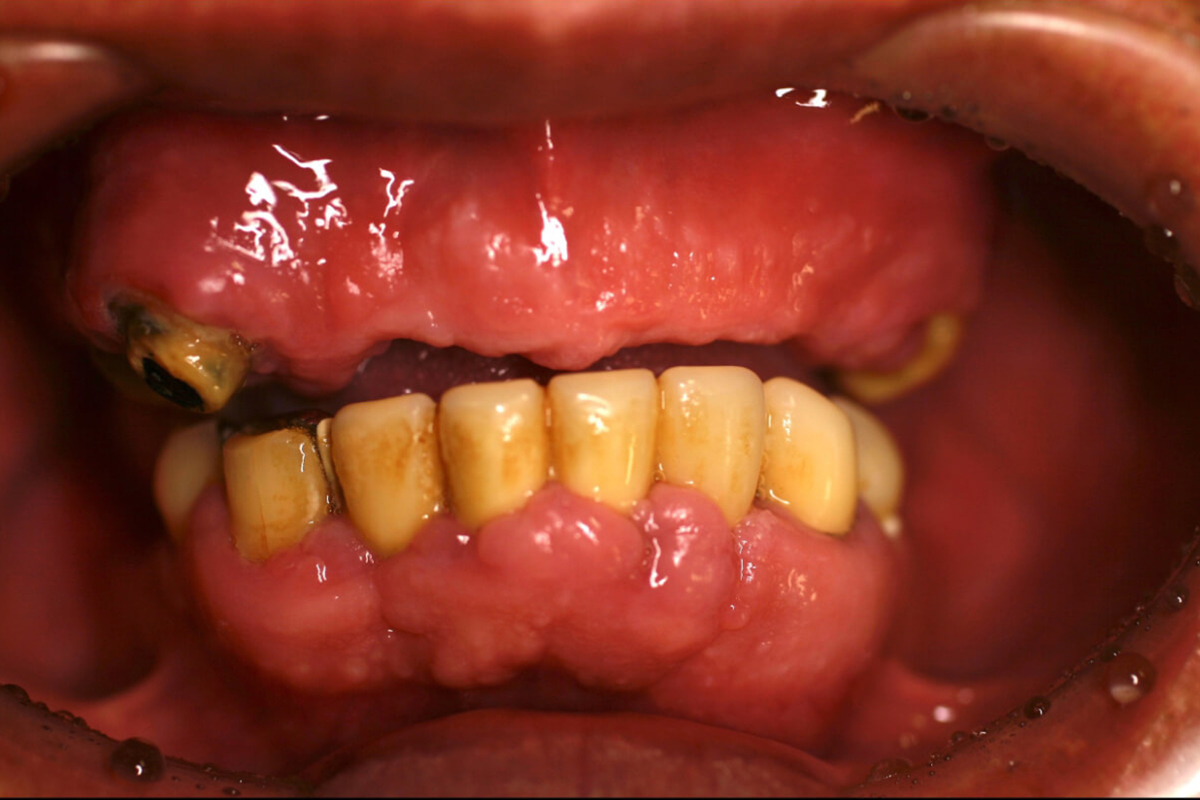

- ⻭⾁が痛くて⼊れ⻭で咬めない。

- ⻭⾁の炎症が著しく不適合の被せ物を外して⻭周病治療を⾏った。

噛み合わせを正しい位置へと誘導後、炎症が改善されたところで、上顎は総義⻭、下顎は特殊義⻭(コーヌス)にて安定するようにかみ合わせ治療を⾏った。